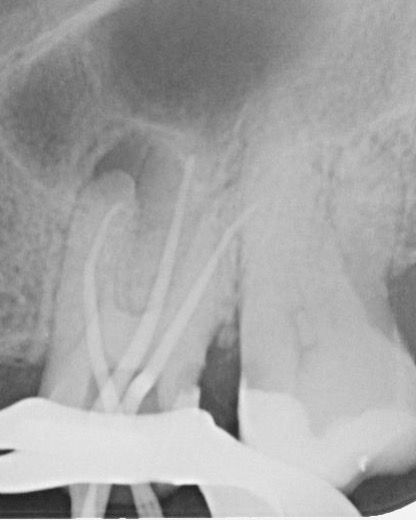

Tedavi esnasında dişin meziobukkal kanalının apikal üçlüsünde alet kırığı meydana geldi. İlgili kırık alet bypass yapılmaya çalışıldı ancak başarılı olunamadı ve kanalda basamak oluştu. Dişin vital olduğu da göz önünde bulundurularak kök kanalları doldurularak dişin takibine karar verildi (Şekil 2).

(Şekil 2) 2023 Mayıs Post-Op radyografi

Yaklaşık 9 ay sonra hasta yapılan kontrolde (2024 Şubat) meziobukkal kök ucunda subklinik şekilde seyreden lezyon olduğu görüldü. Ancak hasta mevcut durumda tekrar tedaviyi kabul etmedi (Şekil 3). (Reddetti)

(Şekil 3). 2024 Şubat kontrol meziobukkal kök ucunda periapikal lezyon